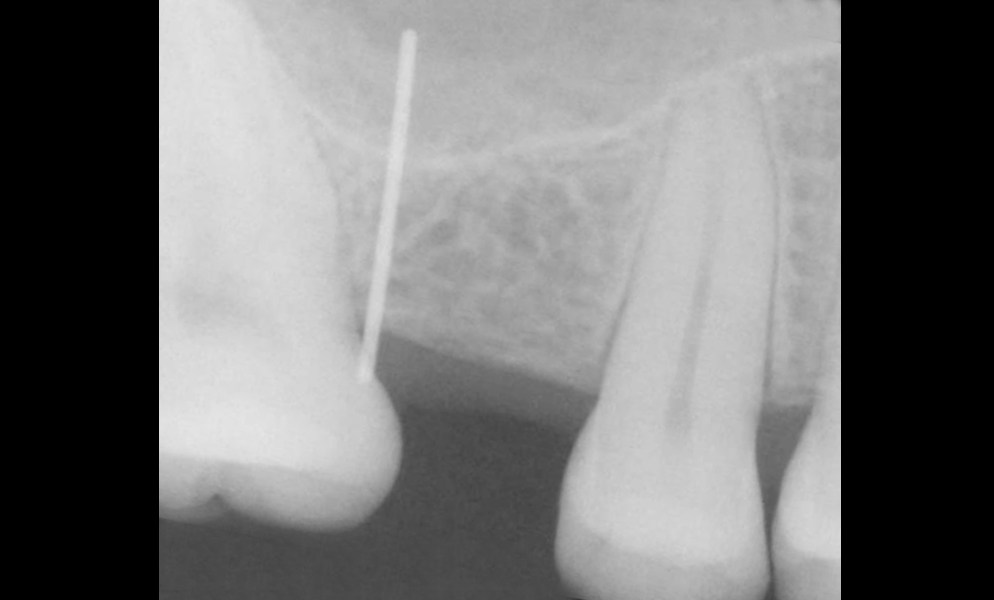

| Before | After |

![]() |

| Single posterior tooth missing space restored with a conventional dental implant (Intra Lock , USA) | |